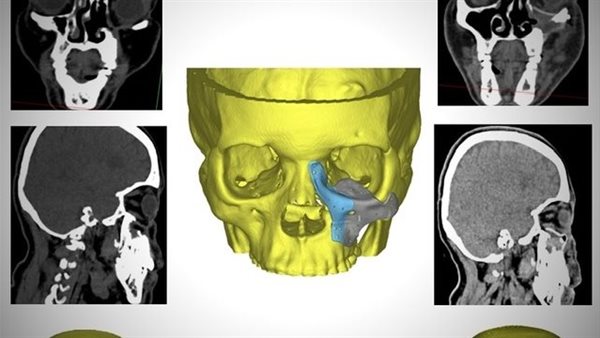

وقال بيان لهيئة الرعاية الصحية، إن السيدة جاءت للمستشفى وهي تعاني من تسوس وتآكل بعظام الوجه وحجاج العين مما استدعى مثول السيدة للعديد من الجراحات التي أدت في النهاية لتشوه عظام الوجه على مدار 4 سنوات من المعاناة، وفقدت السيدة الأمل في مواجهة تحديات كبيرة نتيجة تشوه الوجه ورفض الكثير التدخل الجراحي.

وأضاف البيان، أن قسم جراحة الوجه والفكين بمستشفى الكرنك الدولي اتخذ القرار الطبي بعد استقرار حالة المريضة والمتابعة المستمرة للتأكد من إمكانية التدخل باستخدام التقنيات الحديثة لإعادة البسمة والأمل والثقة للسيدة في علاج التشوه الشديد بالوجه.

وأشار البيان إلى استخدم القسم تصميم معقد مصنوع من مادة الـpeek والمستخدمة حديثًا في استيعاض عظام الوجه وذلك من خلال جراحة دقيقة استغرقت حوالي 6 ساعات.